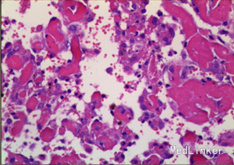

入院诊断:右胫腓骨肿物。入院后行穿刺活检,活检病理示:送检组织见成簇大小不等增生的血管,血管间可见增生的纤维母细胞及硬化的胶原,部分似毛细血管,血管内皮细胞增生,少许呈乳头状伴有纤维素渗出,成簇增生的小血管想骨组织内浸润性生长;结合影像学改变考虑侵袭性血管瘤病。患者予唑来膦酸治疗,治疗后骨化明显,右踝关节胀痛明显缓解。